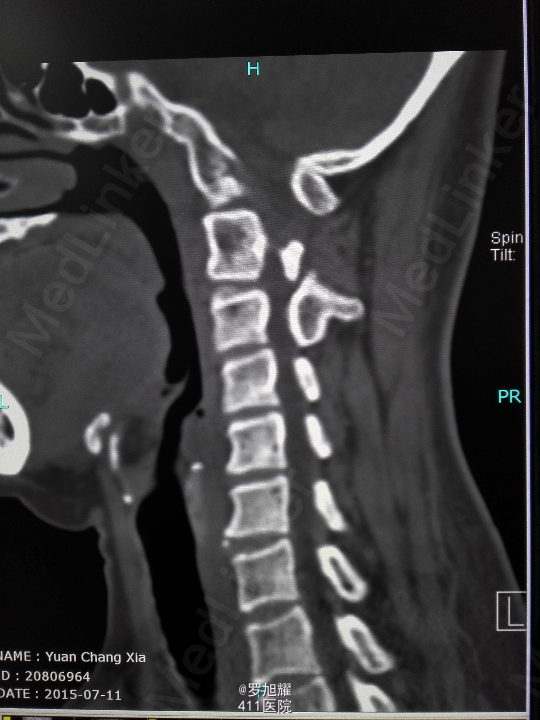

右侧躯体麻木1年,右上肢及下肢麻木2月余。 查体:颈椎活动受限,右上肢肘关节以远痛温觉减退,右侧胸4平面以下痛温觉及触觉减退,四肢肌力尚可,右侧霍夫曼征阳性,右侧上下肢所有腱反射亢进。 颈椎X线示:颈2椎板棘突缺如,颈3棘突肥大增高。 颈椎CT示:颈2椎板棘突缺如,颈3棘突肥大增高,颈2/3椎间盘突出,左侧颈2残留部分椎板进入椎管。枢椎齿突增生,寰枢关节退变。 颈椎MRI示:颈2/3椎间盘突出,左侧颈2椎板进入椎管,颈髓受压变性。

查体:颈椎活动受限,右上肢肘关节以远痛温觉减退,右侧胸4平面以下痛温觉及触觉减退,四肢肌力尚可,右侧霍夫曼征阳性,右侧上下肢所有腱反射亢进。 颈椎X线示:颈2椎板棘突缺如,颈3棘突肥大增高。 颈椎CT示:颈2椎板棘突缺如,颈3棘突肥大增高,颈2/3椎间盘突出,左侧颈2残留部分椎板进入椎管。枢椎齿突增生,寰枢关节退变。 颈椎MRI示:颈2/3椎间盘突出,左侧颈2椎板进入椎管,颈髓受压变性。

诊断为:颈椎先天畸形、颈2/3椎间盘突出伴不全瘫。 因寰枢关节退变,颈椎活动已部分受限,而且枢椎椎板棘突缺如,稳定性差,决定后路减压枕颈融合。